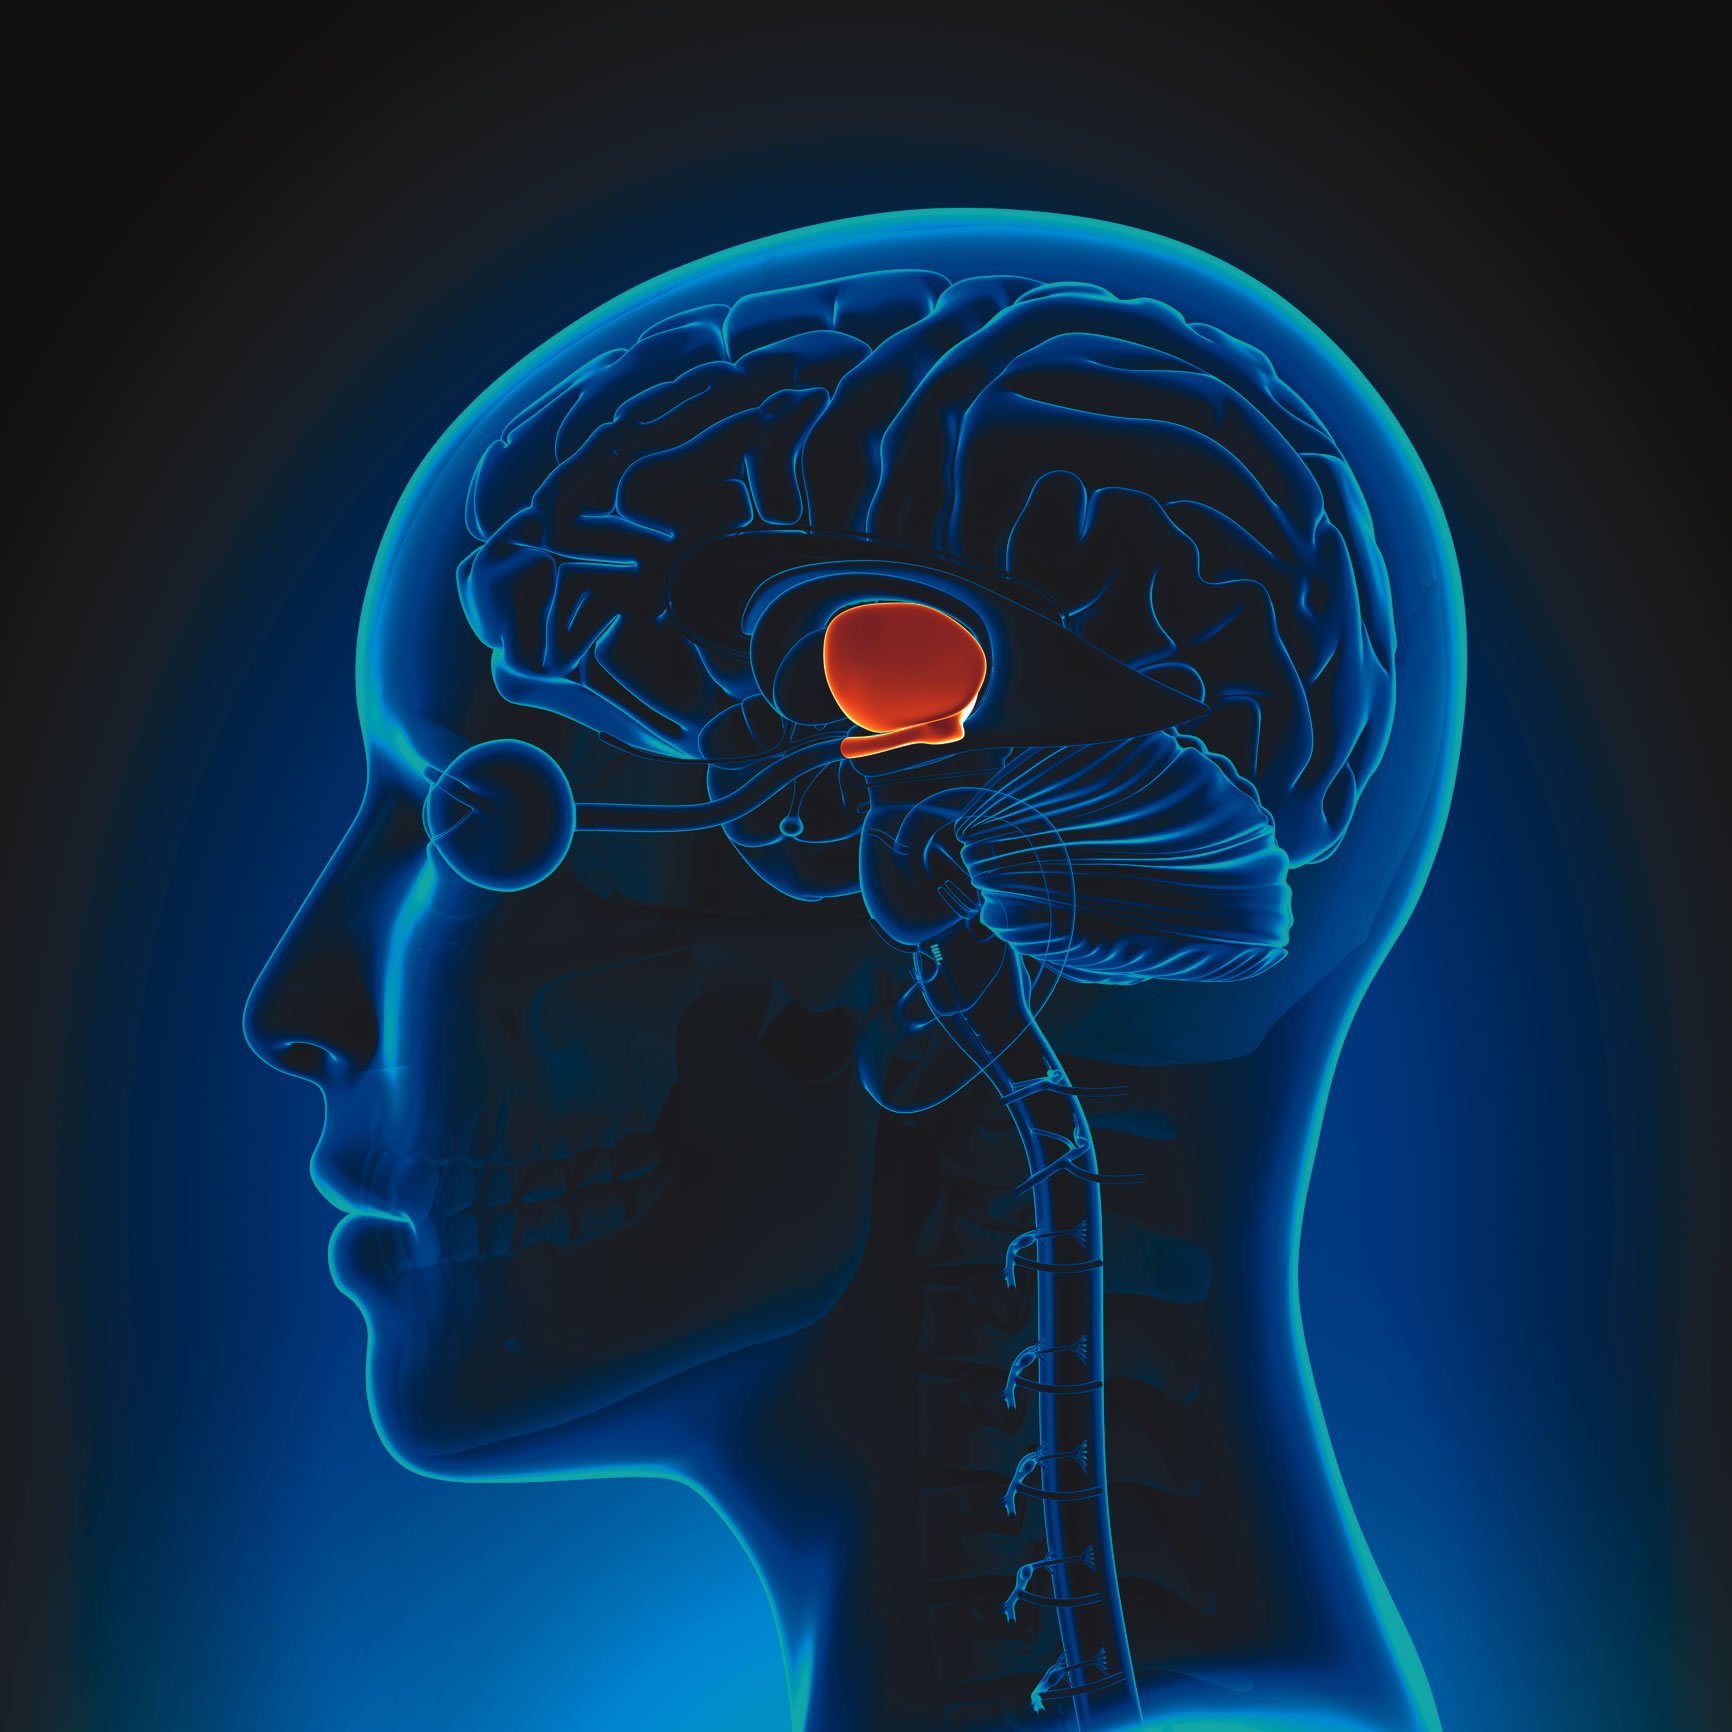

Target Discovered: In April of 2018, Kong and his team published a study in the journal Nature which reported that agouti-related peptide (AgRP) neurons in a region of the brain called the hypothalamus are responsible for leptin’s ability to regulate both energy balance and blood sugar control. Deleting the leptin receptors on AgRP neurons caused severe obesity and diabetes. “Without leptin, AgRP neurons are activated,” says Kong. “Blocking those AgRP neurons reverses the excessive hunger that comes with untreated diabetes, and it reduces high blood sugar.” Kong’s research was also able to shed light on the mechanisms behind leptin resistance.